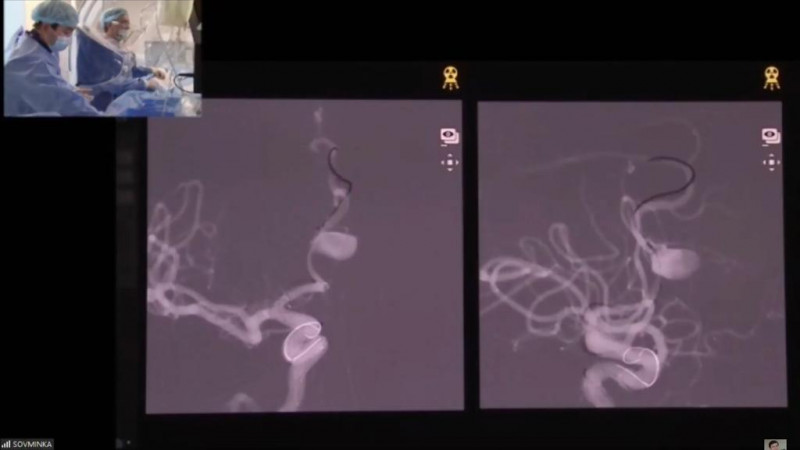

В онлайн-нейрокурсе поучаствовали более 800 участников за два дня. Было проведено 4 показательные операции, которые транслировались в прямом эфире с объяснением техники проведения операций на английском и русском языках. Использована новая биплановая ангиографическая система Phillips Azurion 7, суперсовременная эндоскопическая система Richard Wolt, операционный микроскоп.